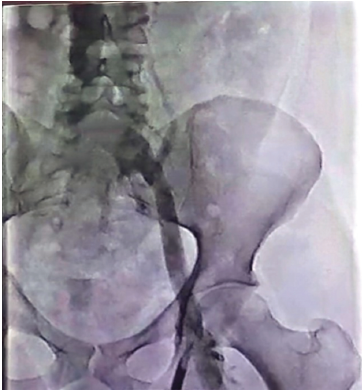

The lower extremity venography revealed complete stenosis at the level of the right femoral vein and partial thrombus in the left common iliac vein with collaterals (Figure 1). On cystoscopy, the urethra was normal in its entire length, and bladder capacity under general anesthesia was 1000 mL.

Figure 1. Partial Thrombus in Left Common Iliac Vein